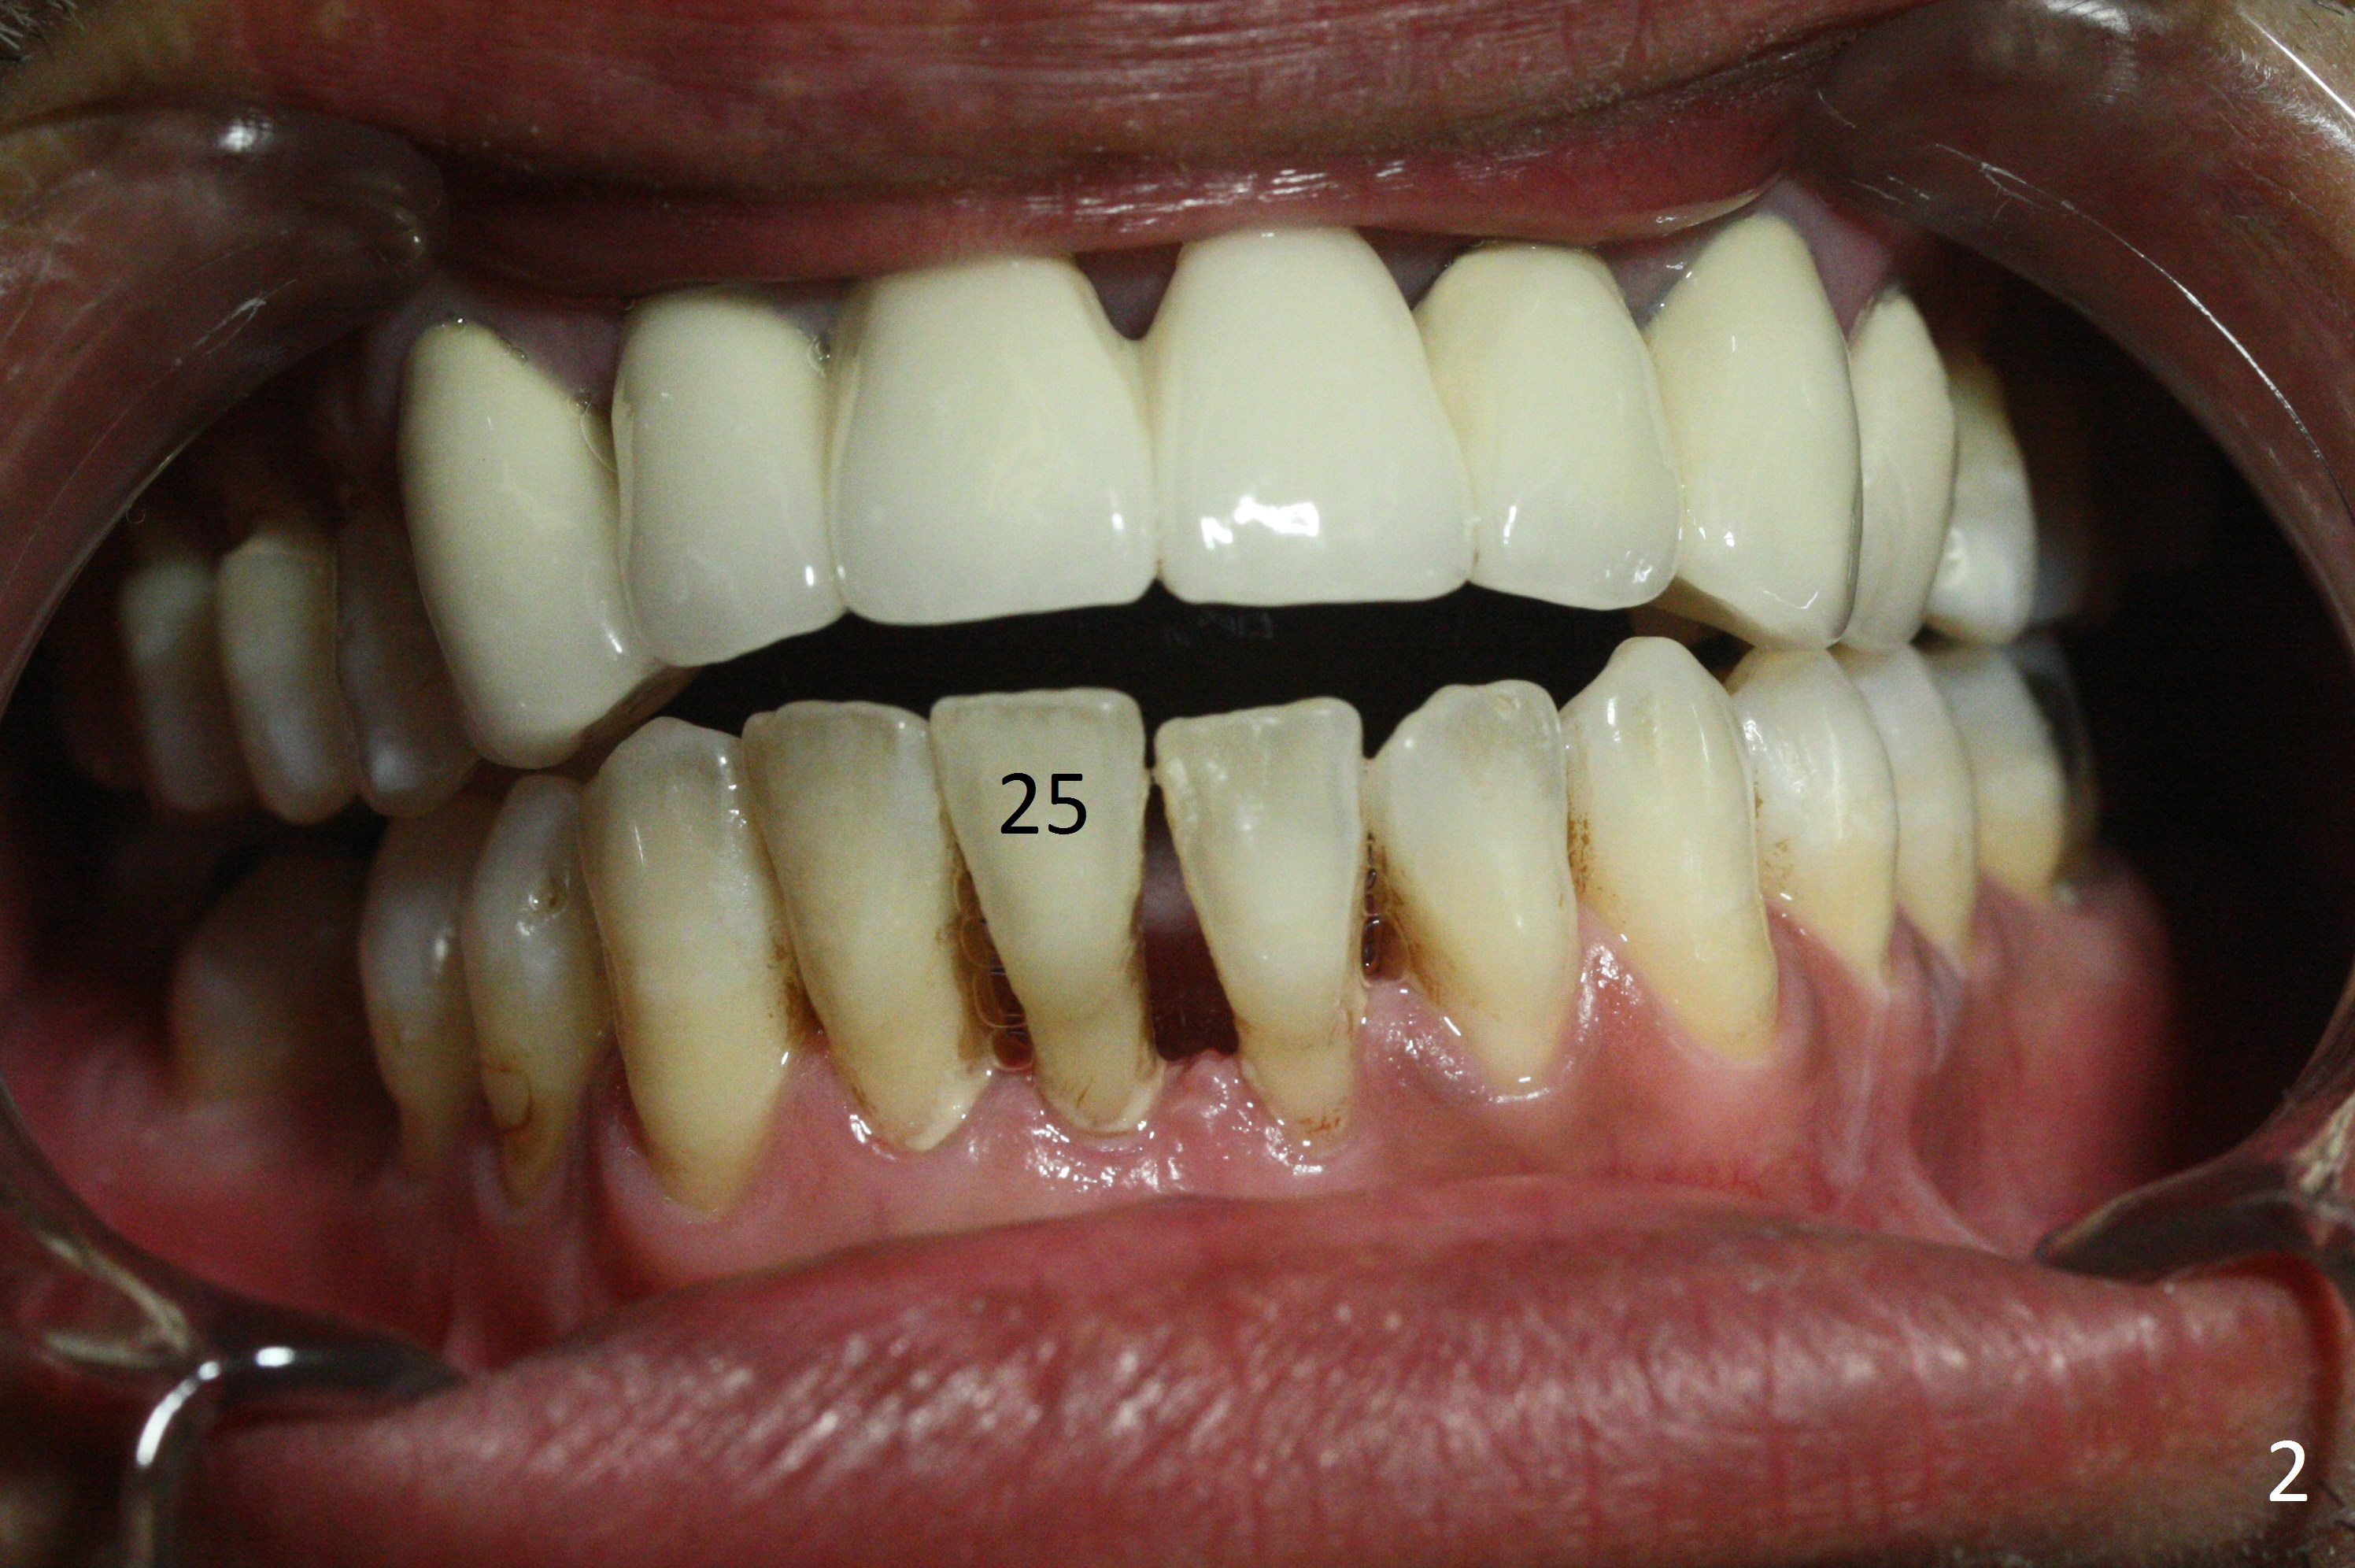

A 48-year-old man is determined to have implants for mobile teeth #14 and 25 (Fig.1).  He is not pleased with the upper anterior FPD because of difficulty in cleaning.  In addition to severe gingival recession (Fig.2), there is an abscess lingual to the tooth #25 (Fig.3).   The latter should be associated with lingual plate defect.  Osteotomy should be initiated in the center of the socket, in contrast to usual lingual starting point.  A 3x16(4) mm 1-piece implant is to be placed unless the socket is small buccolingually or mesiodistally.  Take PA immediately after his arrival for surgery to determine the mesiodistal width and the gingival thickness.  The 2nd parameter will decide what parameter of the implant?